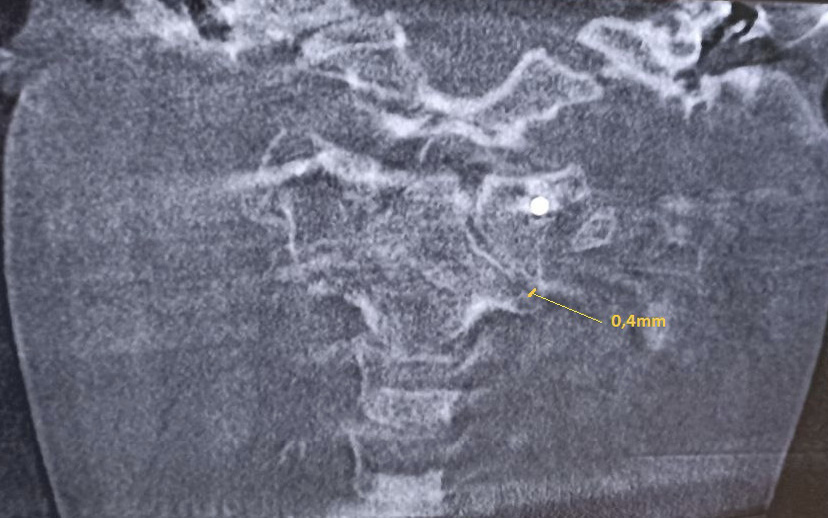

Клиническое наблюдение 1

Пациент В. 9 лет обратился с жалобами на боли и вынужденное положение головы в виде наклона вправо. Из анамнеза, со слов матери, данное состояние возникло на фоне проведенной эндоскопической аденотомии и тимпаноскопии справа около 3 недель назад. На 2-е сутки после проведенного вмешательства, со слов матери, у ребенка появилось вынужденное положение головы в виде наклона вправо и постоянные боли постепенного нарастающего характера по боковой поверхности шеи справа. По данному поводу спустя 7 дней мальчик был консультирован у оперирующего хирурга, который расценил данную ситуацию как допустимые изменения послеоперационного характера. В связи с отсутствием очевидных улучшений мать ребенка приняла решение о необходимости обращения к врачу травматологу-ортопеду. При первичном осмотре ребенка отмечался вынужденный наклон головы вправо до угла в 54°, боли при пальпации по боковой поверхности шеи справа (6-7 баллов по Визуально-аналоговой шкале). Пассивные движения в шейном отделе позвоночника были представлены безболезненным наклоном вперед в пределах 10°, наклоном назад в пределах 3°, наклонами вправо и влево в пределах 5°. Активные движения в шейном отделе позвоночника были представлены в виде безболезненного наклона вперед в пределах 15°, назад в пределах 5-7°, наклонов вправо и влево в пределах 7–10 градусов. Превышение представленных объемов пассивных и активных движений вызывало усиление болей, ротационные движения осуществить не удалось. По остальным отделам костно-мышечной системы отклонения не выявлены. С учетом клинической картины было принято решение выполнить КЛКТ, по результатам которой зафиксировано следующее: ротация атланта вправо вокруг вертикальной оси без передней дислокации. Рентгеновская щель срединного атлантоаксиального сустава не расширена, равна 2,5 мм, что соответствует возрастной норме. Суставные рентгеновские щели латеральных атлантоаксиальных суставов асимметричны: справа 3,1 мм, слева 1,5 мм. Расстояние между медиальными краями боковых масс атланта и зубом аксиса: справа – 2,4 мм, слева – 8,9 мм (рис. 1). Определяется боковое смещение атланта влево: нижняя суставная поверхность левой боковой массы атланта смещена на 4,5 мм влево относительно суставной поверхности аксиса.

Рис. 1. Конусно-лучевая компьютерная томография краниовертебральной области, фронтальный срез на уровне зубовидного отростка С2 позвонка. Методика измерения соотношений в латеральных атланто-аксиальных суставах